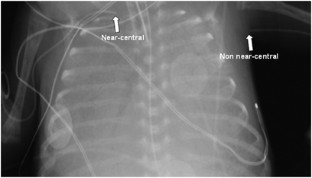

A retrospective, observational study was conducted. The PICCs were catheters whose tip terminated in the vena cavae, and PINCCs were defined as those whose tip fell short of this location. Complication rates were assessed using generalized estimating equations modeling.

Colacchio, K., Deng, Y., Northrup, V. et al. Complications associated with central and non-central venous catheters in a neonatal intensive care unit. J Perinatol 32, 941–946 (2012). https://doi.org/10.1038/jp.2012.7